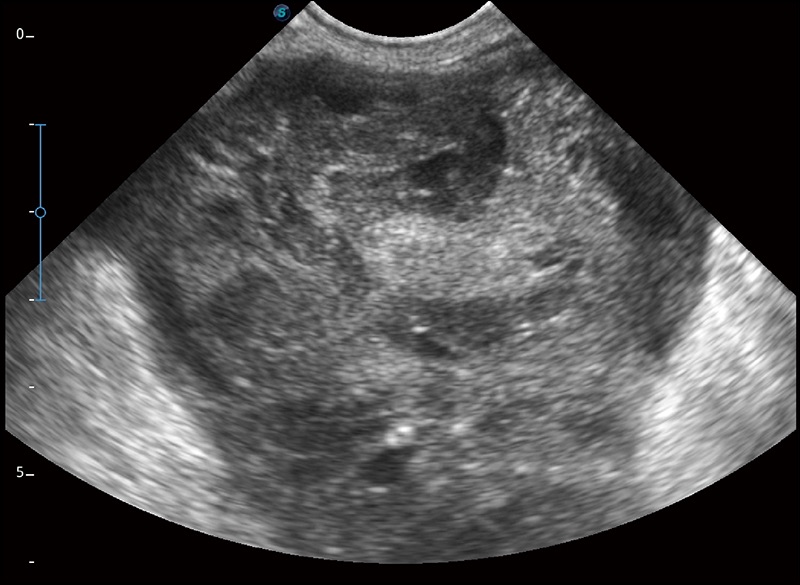

实时宽景成像

可实时观察感兴趣区域和病变位置